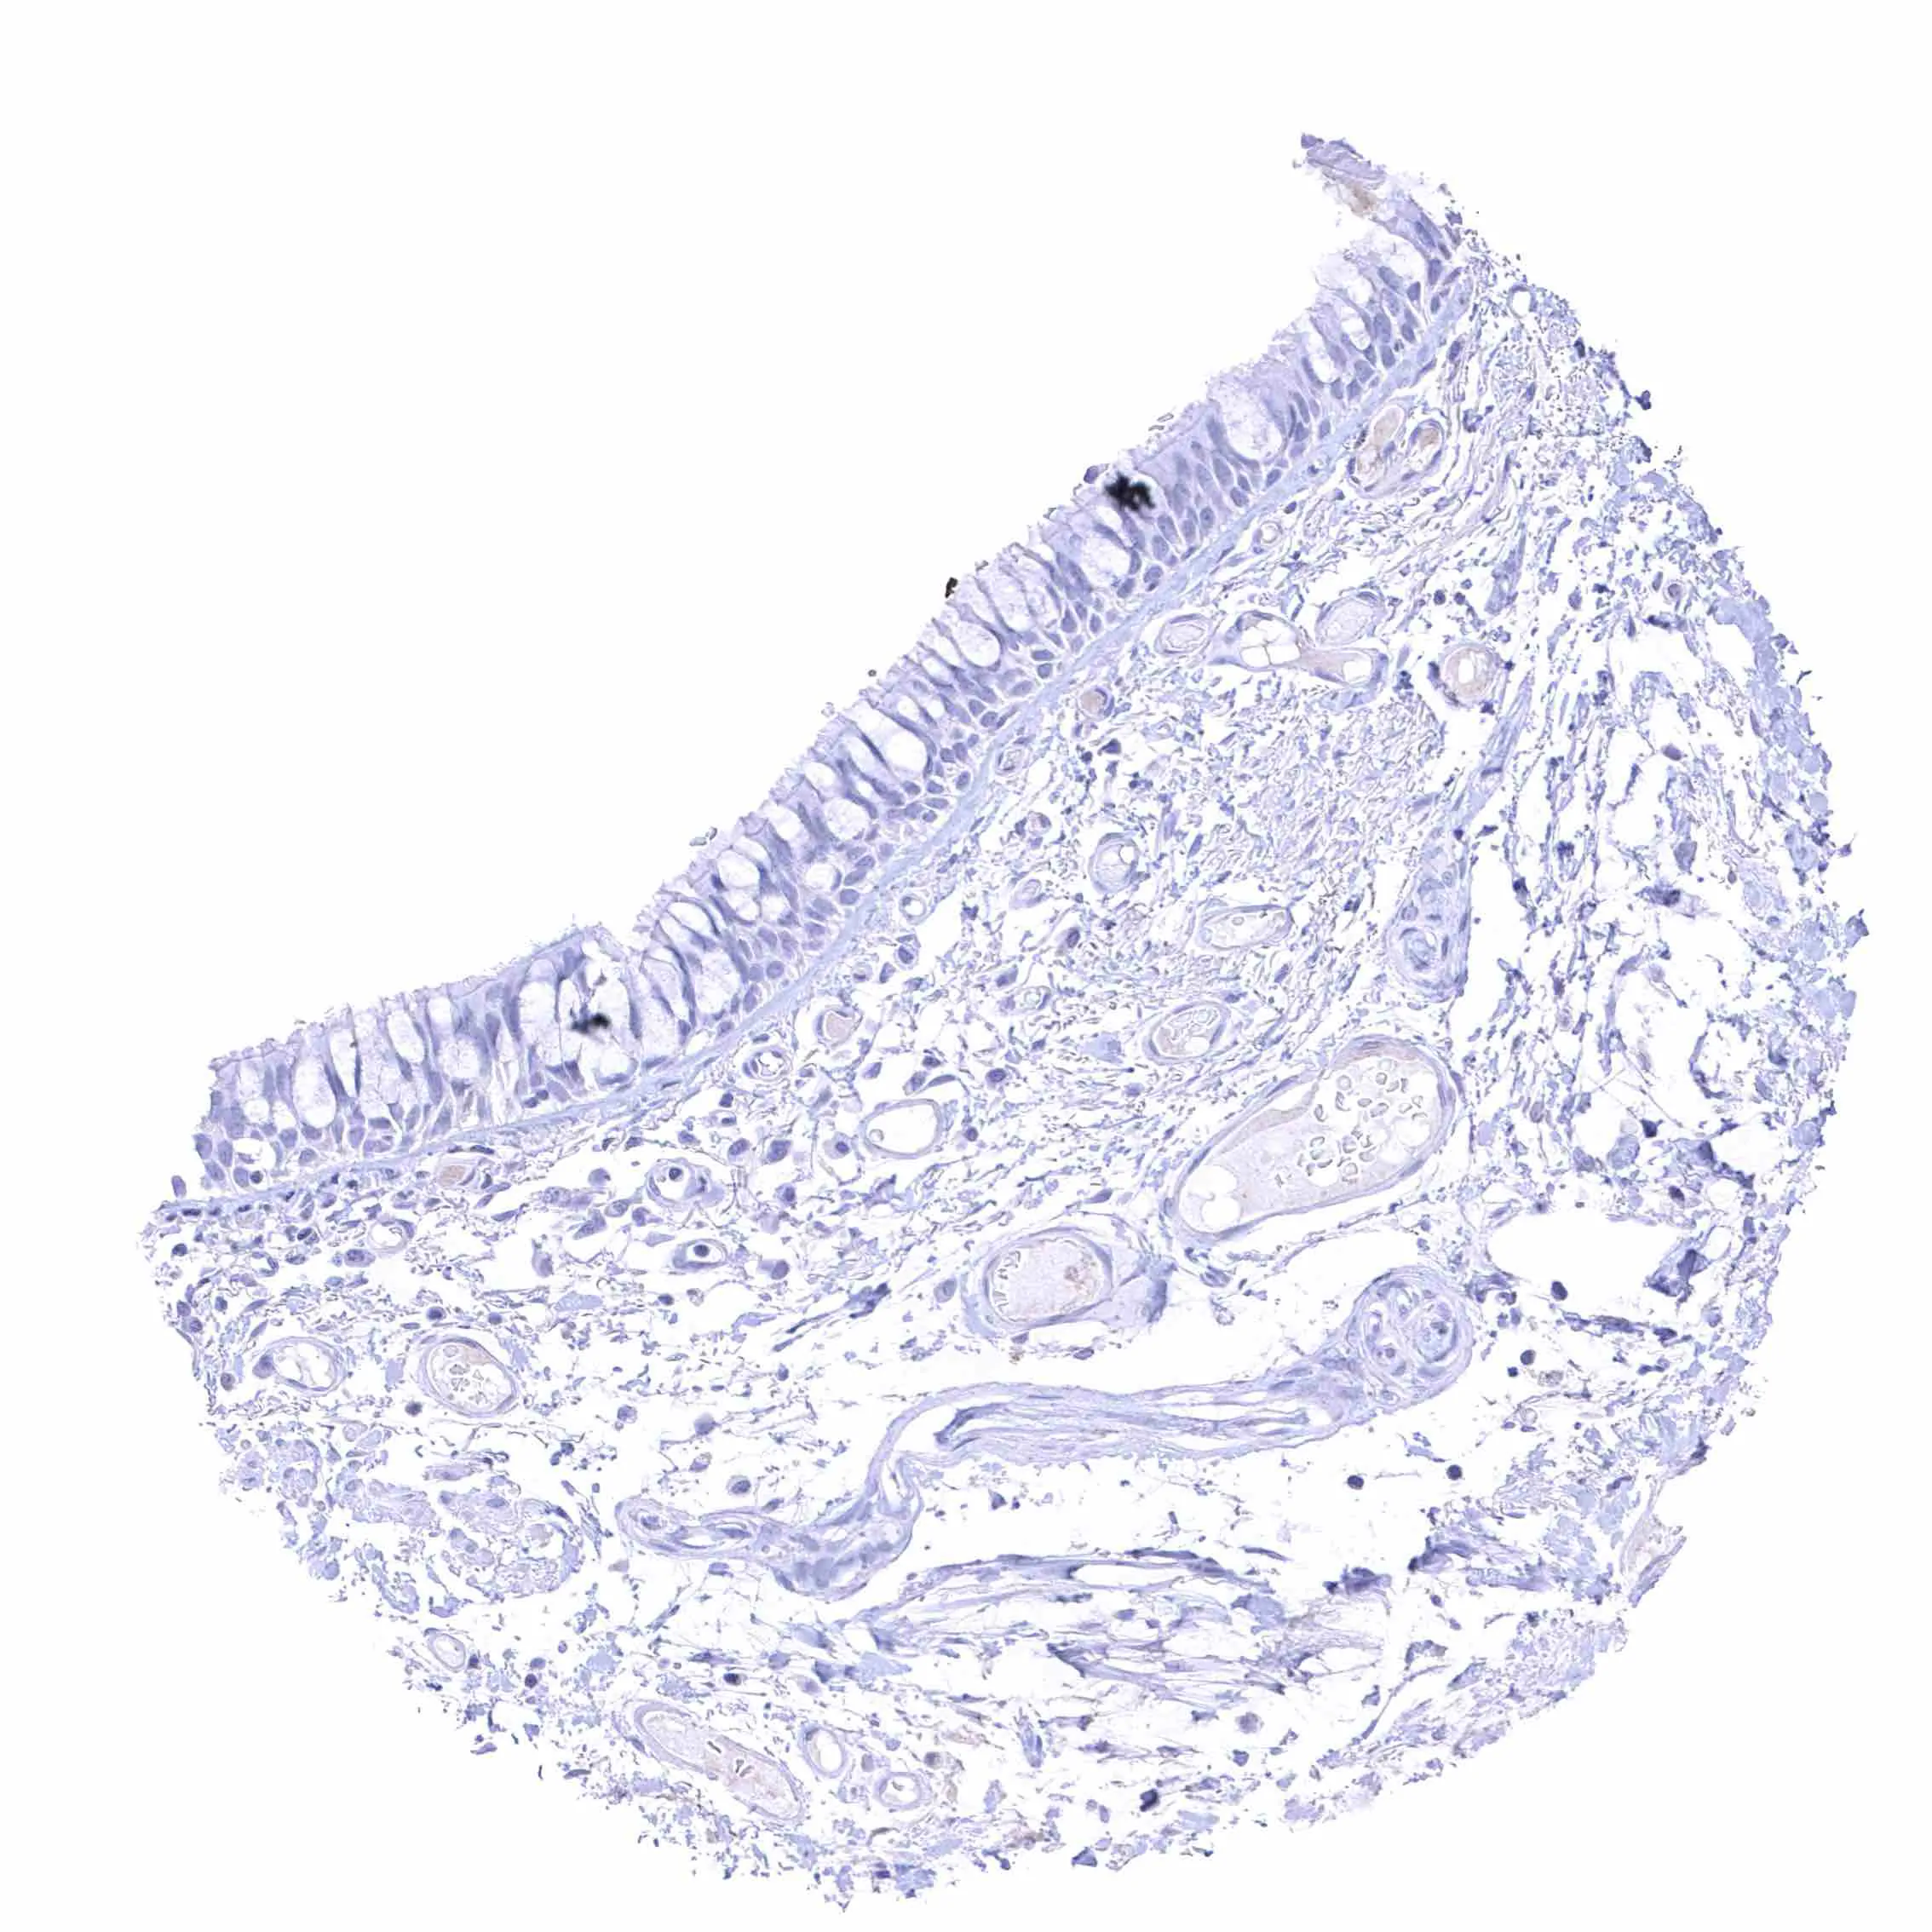

Skin, hairfollicel and sebaceous glands